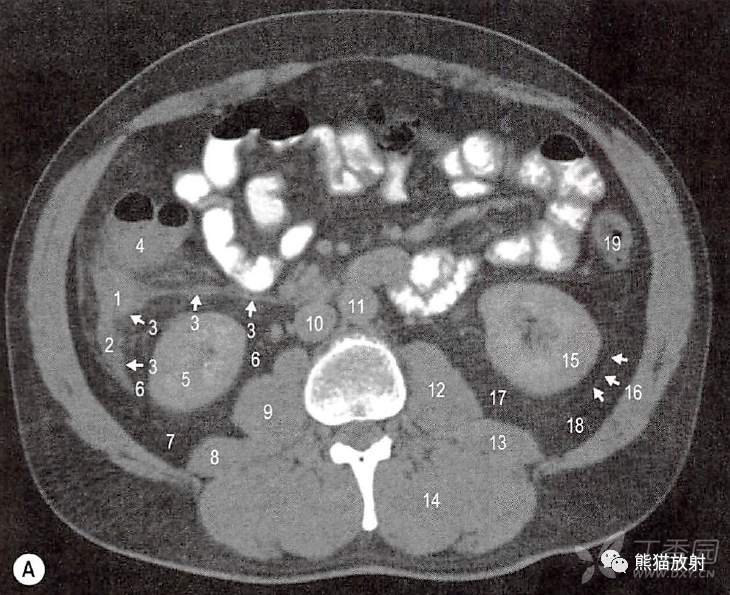

43岁男性盲肠后位阑尾炎。右结肠周隙炎性积液和粘连。可见右上肾周筋膜和右结肠系膜(Toidt’s筋膜) 融合

A.经过阑尾的横断面;1.增厚和发炎的阑尾;2.右结肠周隙后面的炎性积液,右肾周间隙前部;3.肾周前筋膜(与结膜后筋膜/结肠系膜融合);4.盲肠/升结肠;5.右肾实质;6.右肾周间隙;7.右肾旁后间隙(肾后筋膜难以辨认);8.右腰方肌;9.右腰大肌;10.下腔静脉;11.腹主动脉;12.左腰大肌;13.左腰方肌;14.左竖脊肌组;15.左肾实质;16.左肾后筋膜;17.左肾周间隙;18,左肾旁后间隙;19.降结肠。

B.经过阑尾的冠状面;1.增厚发炎的盲肠后位阑尾;2.炎性液体和水肿沿右结肠系膜到肠系膜扩展;3.增大的回肠结肠淋巴结;4.右结肠系膜的炎性积液;5.下腔静脉一肝后段;6.下腔静脉一肝下腹膜段;7.下腔静脉一肾段;8.下腔静脉一肾下段;9.左肾静脉;10.肠系膜上动脉;11.腹腔干;12.腹主动脉;13.右髂总动脉;14.左髂总动脉;15.胰尾